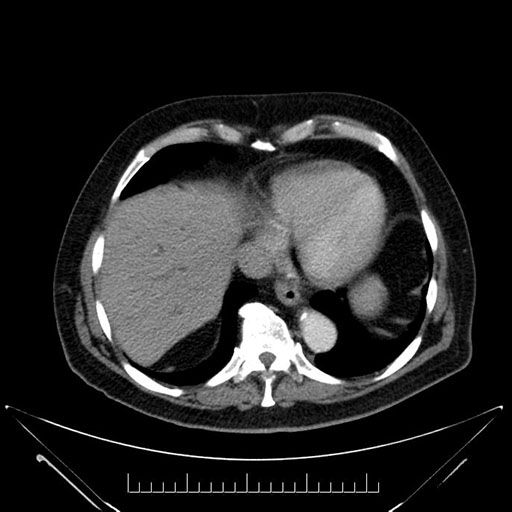

Imaging Analysis

Look through the patient's CT scan to identify any areas of concern for the necessary procedure.

Based on your CT findings, which issue(s) would give reason for "planned slowing down moment(s)" in this case?

Considering a standard Whipple procedure, what step(s) of the operation would you do differently in this case?